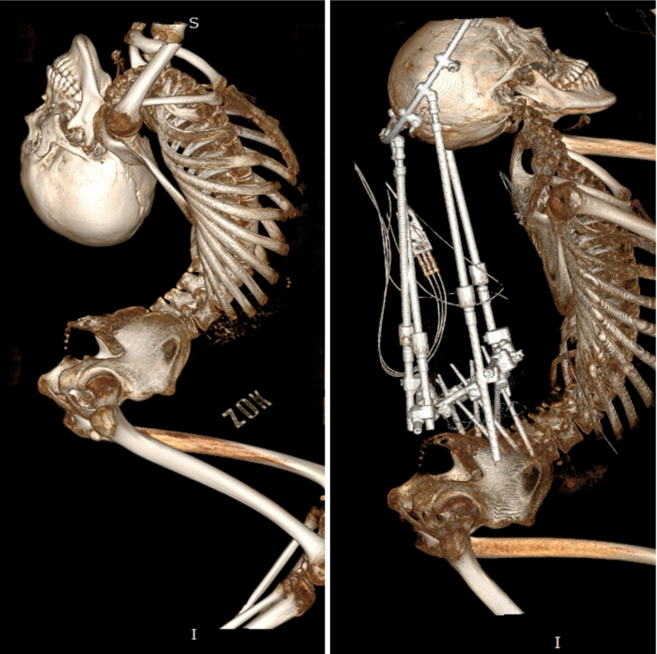

姜延琛的脊柱影像

第一次手术前后的对比

姜延琛第一次手术前后的CT扫描图对比